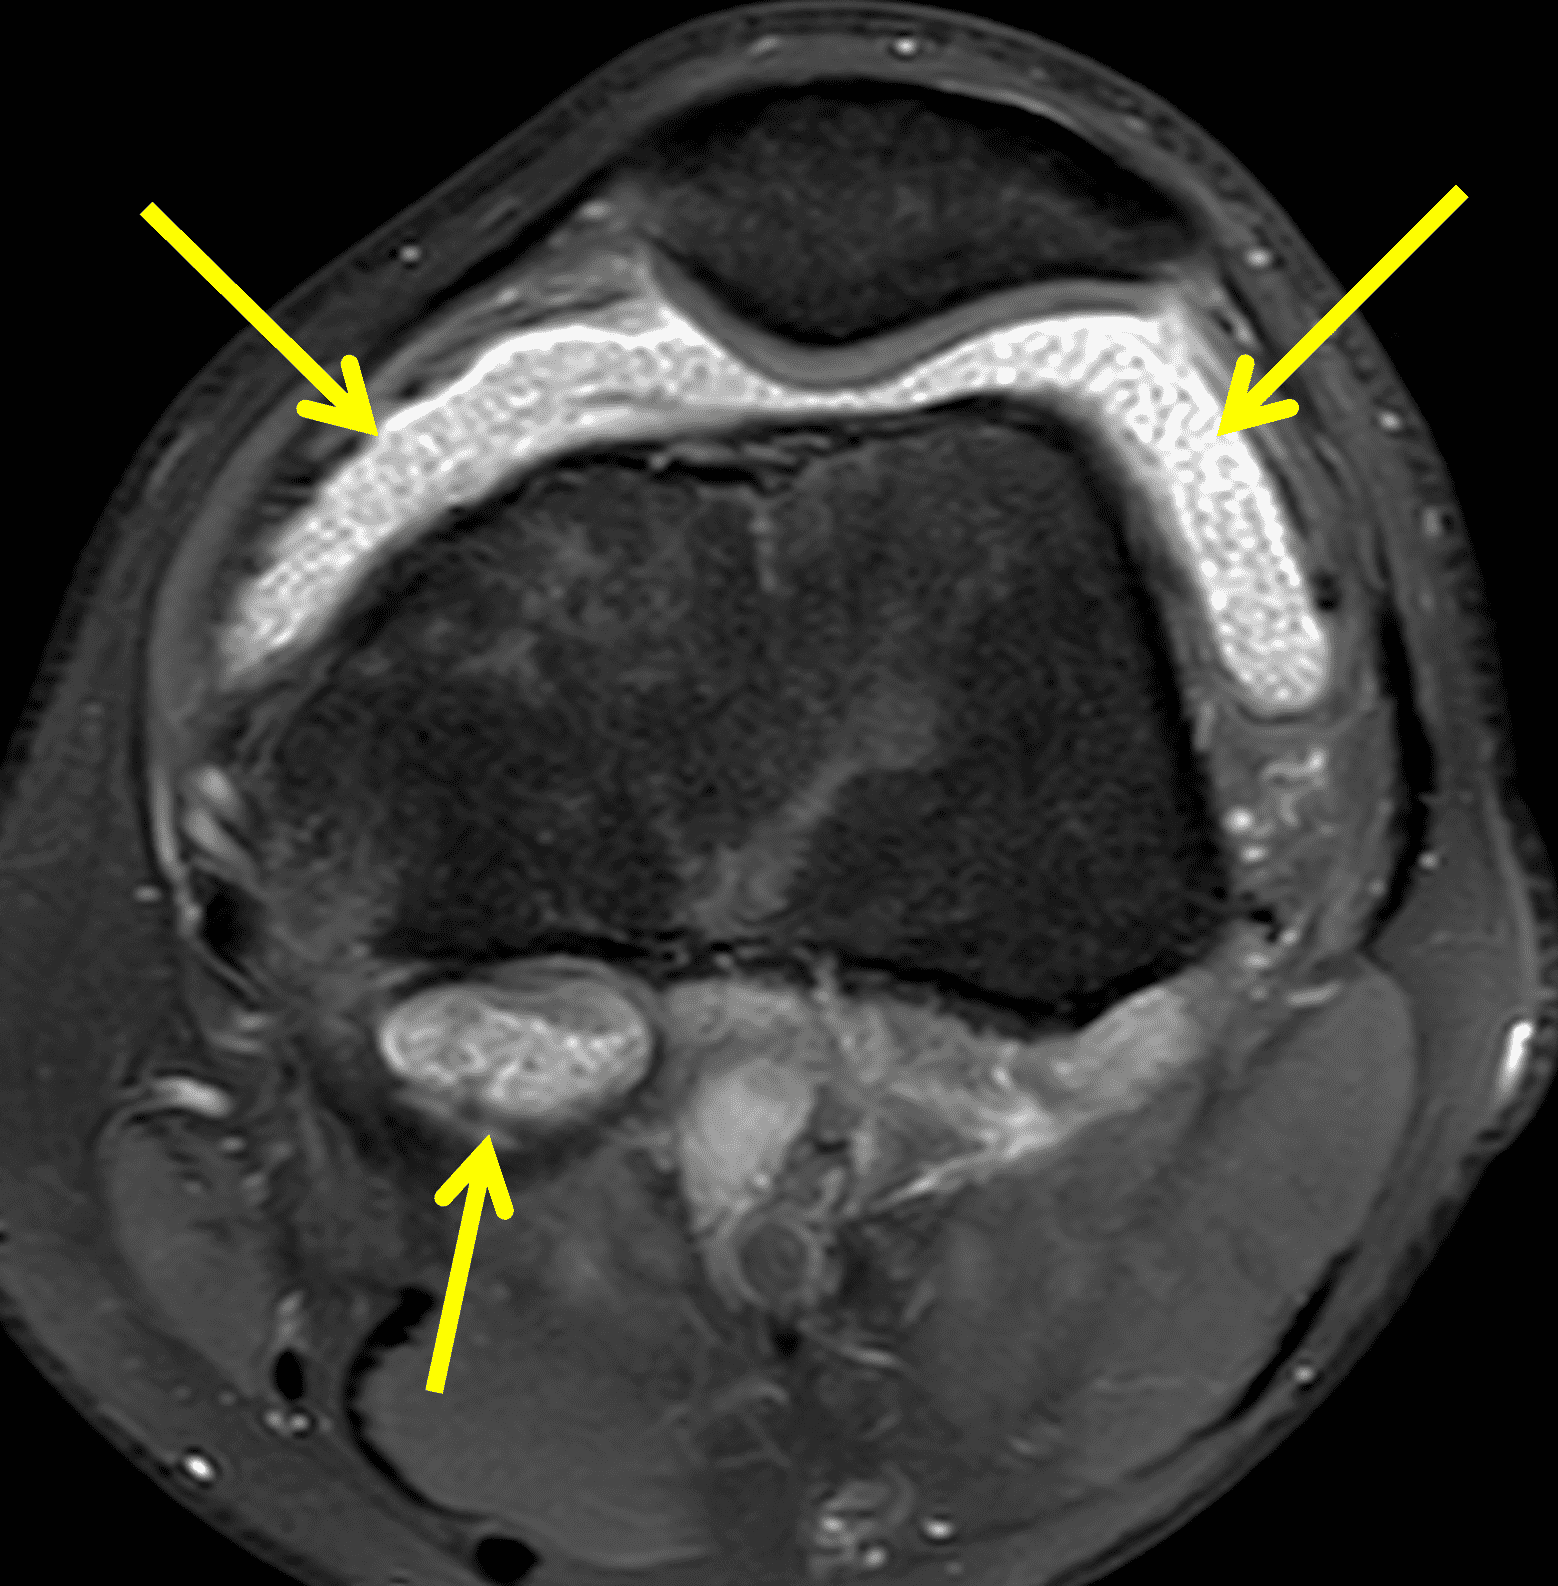

Figure 4: Lyme arthritis. Fat-suppressed, fluid-sensitive images. (4A) Transverse image shows severe proliferative synovitis in the anterior and posterior joint recesses (arrows). Note the lack of surrounding subcutaneous edema. (4B) In addition to synovitis, the sagittal image shows multiple reactive lymph nodes (red arrows) and popliteal myositis (white arrow). (4C) Coronal image also shows patchy non-joint centered marrow edema in the distal femur and proximal tibia (asterisks), which is uncommon in Lyme disease compared to acute septic arthritis.

Pediatric patients often present with a more acute clinical picture including fever, difficulty weight-bearing, elevated serum inflammatory markers, and elevated synovial white blood cell count, all of which can also be seen in the setting of acute septic arthritis due to other bacteria.5,9,12 Several studies have identified MR findings that help distinguish Lyme arthritis from septic arthritis for clinical decision-making. Both groups of patients will have synovitis and an effusion related to synovial inflammation and hyperemia. However, subcutaneous edema is highly associated with septic arthritis (Figure 5) and uncommon in Lyme arthritis. Marrow edema and erosions are much more common in septic arthritis, while osteomyelitis – actual infection of the bone – only occurs septic arthritis.2,3,9 Myositis can be seen in both conditions, but severe diffuse myositis is more highly correlated with septic arthritis (Figure 5).2